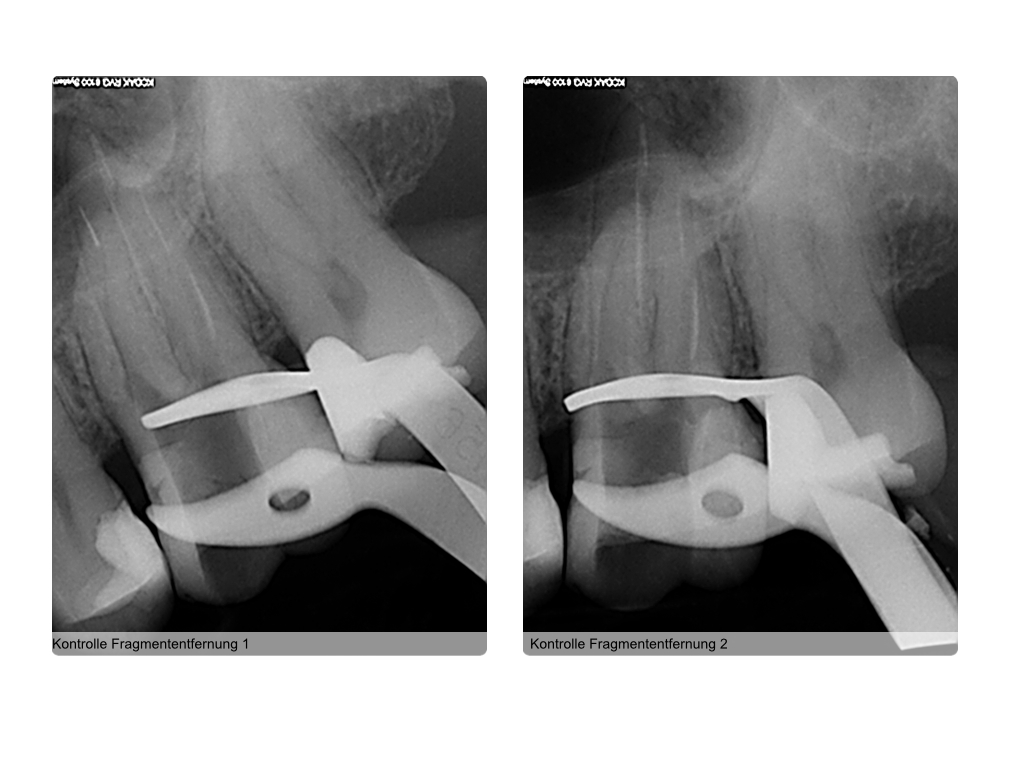

Instrumentenfraktur (3b)